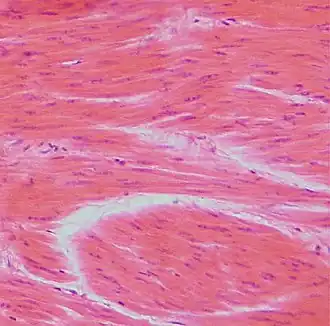

Гладкие мышцы

Гла́дкие мы́шцы — сократимая ткань, в отличие от поперечнополосатых мышц не имеющая поперечной исчерченности.

У некоторых беспозвоночных гладкие мышцы образуют всю мускулатуру тела. У позвоночных они входят в состав оболочек внутренних органов: кишечника, кровеносных сосудов, дыхательных путей, выделительных и половых органов, а также многих желёз. Клетки гладких мышц у беспозвоночных разнообразны по форме и строению; у позвоночных в большинстве случаев веретенообразные, сильно вытянутые, с палочковидным ядром, длиной 50—250 мкм, в матке беременных животных — до 500 мкм; окружены волокнами соединительной ткани, образующими плотный футляр.

Мышечные клетки называются миоцитами. Гладкие миоциты — веретенообразные вытянутые клетки, содержащие одно палочковидное ядро, расположенное в центре. Каждый миоцит окружён базальной мембраной[3].